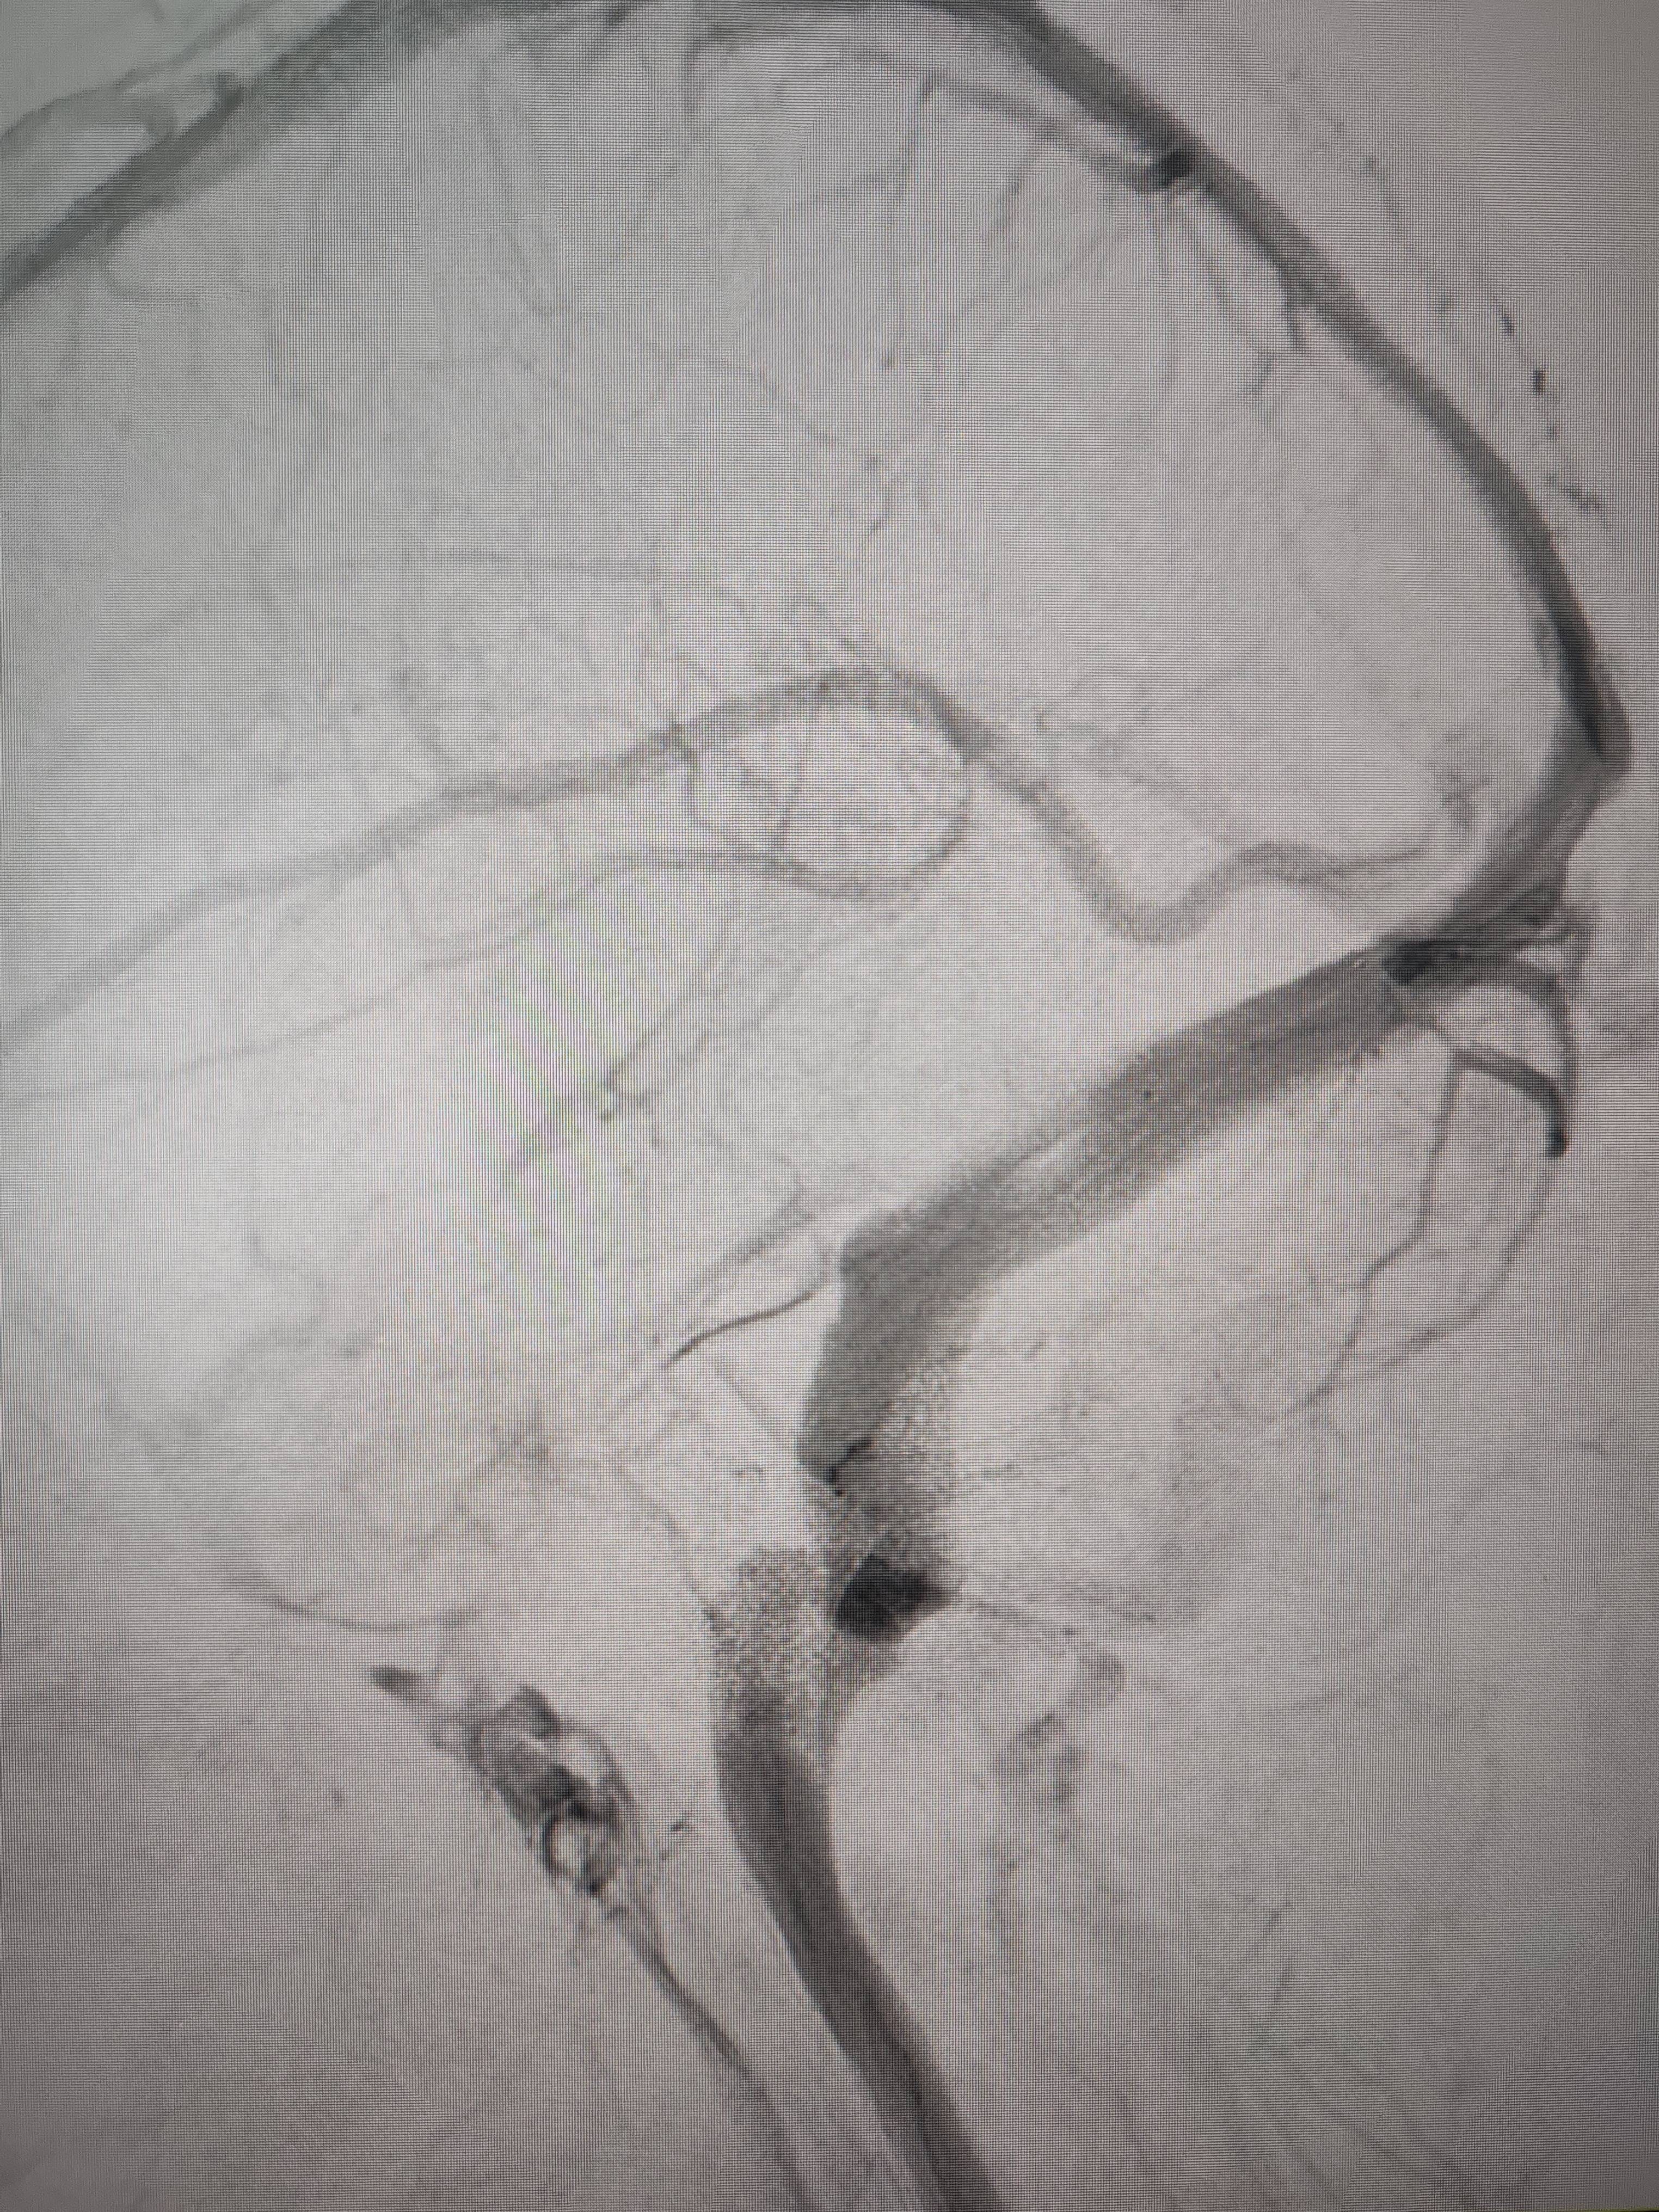

经过静脉窦支架置入手术治疗后,患者的静脉窦“堵点”被打通btc充值。 南方+ 欧阳少伟 拍摄